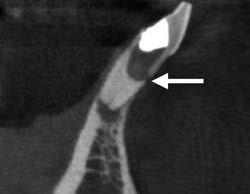

Egy 38 éves nőbeteg a korábban kezelt jobb felső második kisőrlőfogából (1.5) kiinduló mérsékelt fájdalom miatt jelentkezett rendelésünkön. A kórtörténetében jelen panasza szempontjából releváns információ nem szerepelt. A beteg a klinikai vizsgálat során vertikális kopogtatásra enyhe érzékenységet jelzett. A kérdéses fog körül mérhető szondázási mélység és a fogmobilitás fiziológiás volt. Periapicalis röntgenfelvételen egy, a fog gyökércsúcsán túl presszálódott betört gyökérkezelő műszerből származó eszközfragmentumot láttunk (2. a. ábra). A preoperatív CBCT-felvétel a buccalis csontlemez épségét igazolta (2. b-c. ábra). A fog revíziója öt hónappal korábban történt. A már előzőleg gyökérkezelt, gyökértömött, majd revideált 1.5-ös fog esetében a diagnózisunk periodontitis periapicalis symptomatica volt. A periapikális elváltozás kezelése érdekében navigált endodonciai mikrosebészeti beavatkozást végeztünk.

A felső állcsontról intraorális szkent (TRIOS) készítettünk, és az ezáltal kapott STL fájlt (2. d. ábra) a CBCT-felvétel során nyert DICOM fájlokkal a Zirkonzahn.Implant-Planner (Zirkonzahn) szoftverben egyesítettük. A sebészi sablont ebben a programban megterveztük, majd a Meshmixer (Autodesk) szoftver se-

a-m. ábrák: Preoperatív röntgenfelvétel (a) és preoperatív CBCT-felvétel a jobb felső 5-ös (1.5) fogról, sagittalis (b) és axialis (c) nézetek. Az intraorális szkennelés során kapott STL-fájl (d). A 1.5-ös fog navigált endodonciai mikrosebészeti beavatkozásához tervezett sablon (e). A 1.5-ös fog navigált endodonciai mikrosebészeti beavatkozásához nyomtatott sablon (f). Teljes vastagságú mucoperiostealis lebenyt emeltünk (g). A sablont a helyére illesztettük, és a csontablak határait jelöltük (h). A fog gyökerén kívül eső, betört eszköz a 1.5-ös fog periapicalis régiójában (i). Az eltávolított betört eszköz (j). A rezekció, retrográd preparáció és a TotalFill BC RRM Fast Set Putty anyaggal elkészített retrográd gyökértömés utáni röntgenfelvétel (k). A lebenyt varratokkal rögzítettük (l). A kétéves kontroll során készített röntgenfelvétel (m).

gítségével tovább módosítottuk. Az így kapott sebészi sablon egyértelműen meghatározta a periapikális terület eléréséhez szükséges csontablak határait (2. e-f. ábra) Helyi érzéstelenítést követően teljes vastagságú mucoperiostealis lebenyt képeztünk, majd a buccalis csont feltárását követően (2. g. ábra) a sablon segítségével bejelöltük a preparálandó csontablak határait (2. h. ábra). A csontablak kialakítása során Piezotome CUBE LED kézi-darabot alkalmaztunk, majd a leemelését követően a betört eszközt megkerestük (2. i. ábra) és eltávolítottuk (2. j. ábra). A rezekciót ultrahangos megmunkáló fejekkel (ACTEON) végeztük, majd retrográd preparáció következett.

A retrográd gyökértömés elkészítése során TotalFill BC RRM Fast Set Putty-t (FKG) használtunk (2. k. ábra). A lebeny széleit 5/0-s Prolene varratokkal egyesítettük (2. l. ábra). A varratok a műtétet követően 72 órával kerültek eltávolításra. A beteg két évvel később kontrollröntgen készítése céljából érkezett rendelőnkbe. A vizsgálat során a fog tünetmentesnek és funkcióképesnek bizonyult (2. m. ábra).